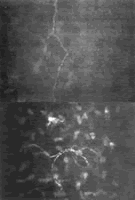

结果表明,与对照组相比,2型糖尿病患者角膜上皮下神经丛神经分支密度、神经纤维长度均减少(图1),差异有统计学意义(P<0.01)。神经纤维的密度仅PDR组显著减少(P<0.01),NPDR和NDR两组减少不明显(P>0.05)。糖尿病患者中,角膜基质内出现神经纤维形态异常(图2)的几率明显高于对照组(P=0.000)。(中华眼科杂志 2006, 42:896)

图1 共焦显微镜观察PDR组患者上皮下神经丛图像×40

图2 共焦显微镜观察PDR组患者角膜基质神经图像示纤细盘旋、弯曲异常走行的神经纤维×40, http://www.100md.com